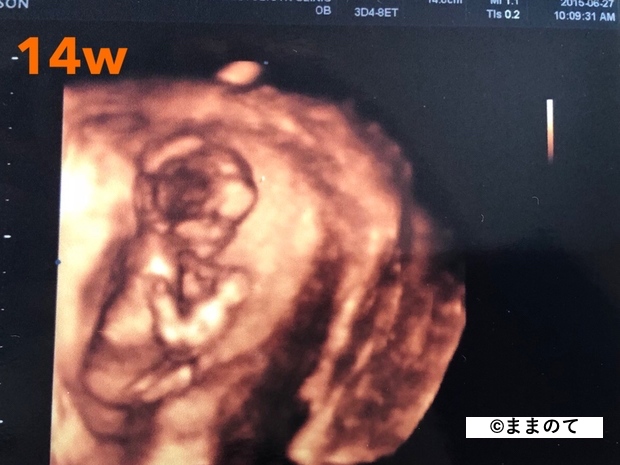

妊娠4ヶ月(12・13・14・15週)

4ヶ月の終わりころには胎盤が完成し始め、成長のスピードが加速する時期です。首を動かせるようになるため、CRLでの測定に誤差が生じるようになります。

身長は15~18cm、体重は約110gに増加します。赤ちゃんはグレープフルーツほどの大きさです。